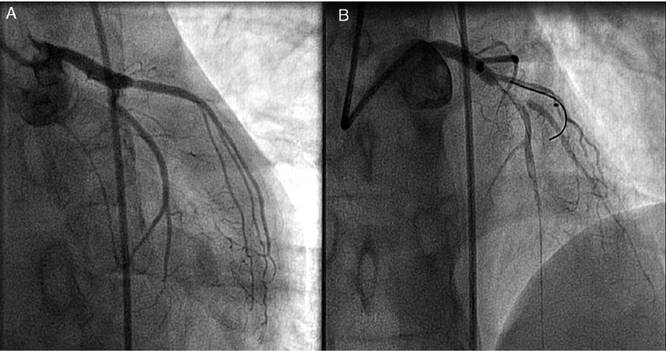

Fue trasladado a urgencias hospitalarias 12 horas después del inicio del dolor, donde se le administró doble antiagregación y heparina de bajo peso molecular y se inició perfusión de nitroglicerina, que debió ser suspendida por hipotensión. La analítica mostró leucocitosis sin neutrofilia y el pico de biomarcadores cardiacos fue CPK 4.631 UI/l y troponina-I 81 ng/l. La radiografía de tórax no reveló signos de insuficiencia cardíaca, mientras que una ecocardiografía transtorácica objetivó una aquinesia anterolateral e inferior medio-apical, con FEVI 30%. La coronariografía preferente mostró una oclusión subaguda total de arteria descendente anterior proximal-media, que fue tratada mediante el implante de un stent farmacoactivo, con buen resultado angiográfico (fig. 1,) (Anexo material disponible en la web. Vídeo 1).

Figura 1 Oclusión subaguda total de arteria descendente anterior proximal-media.